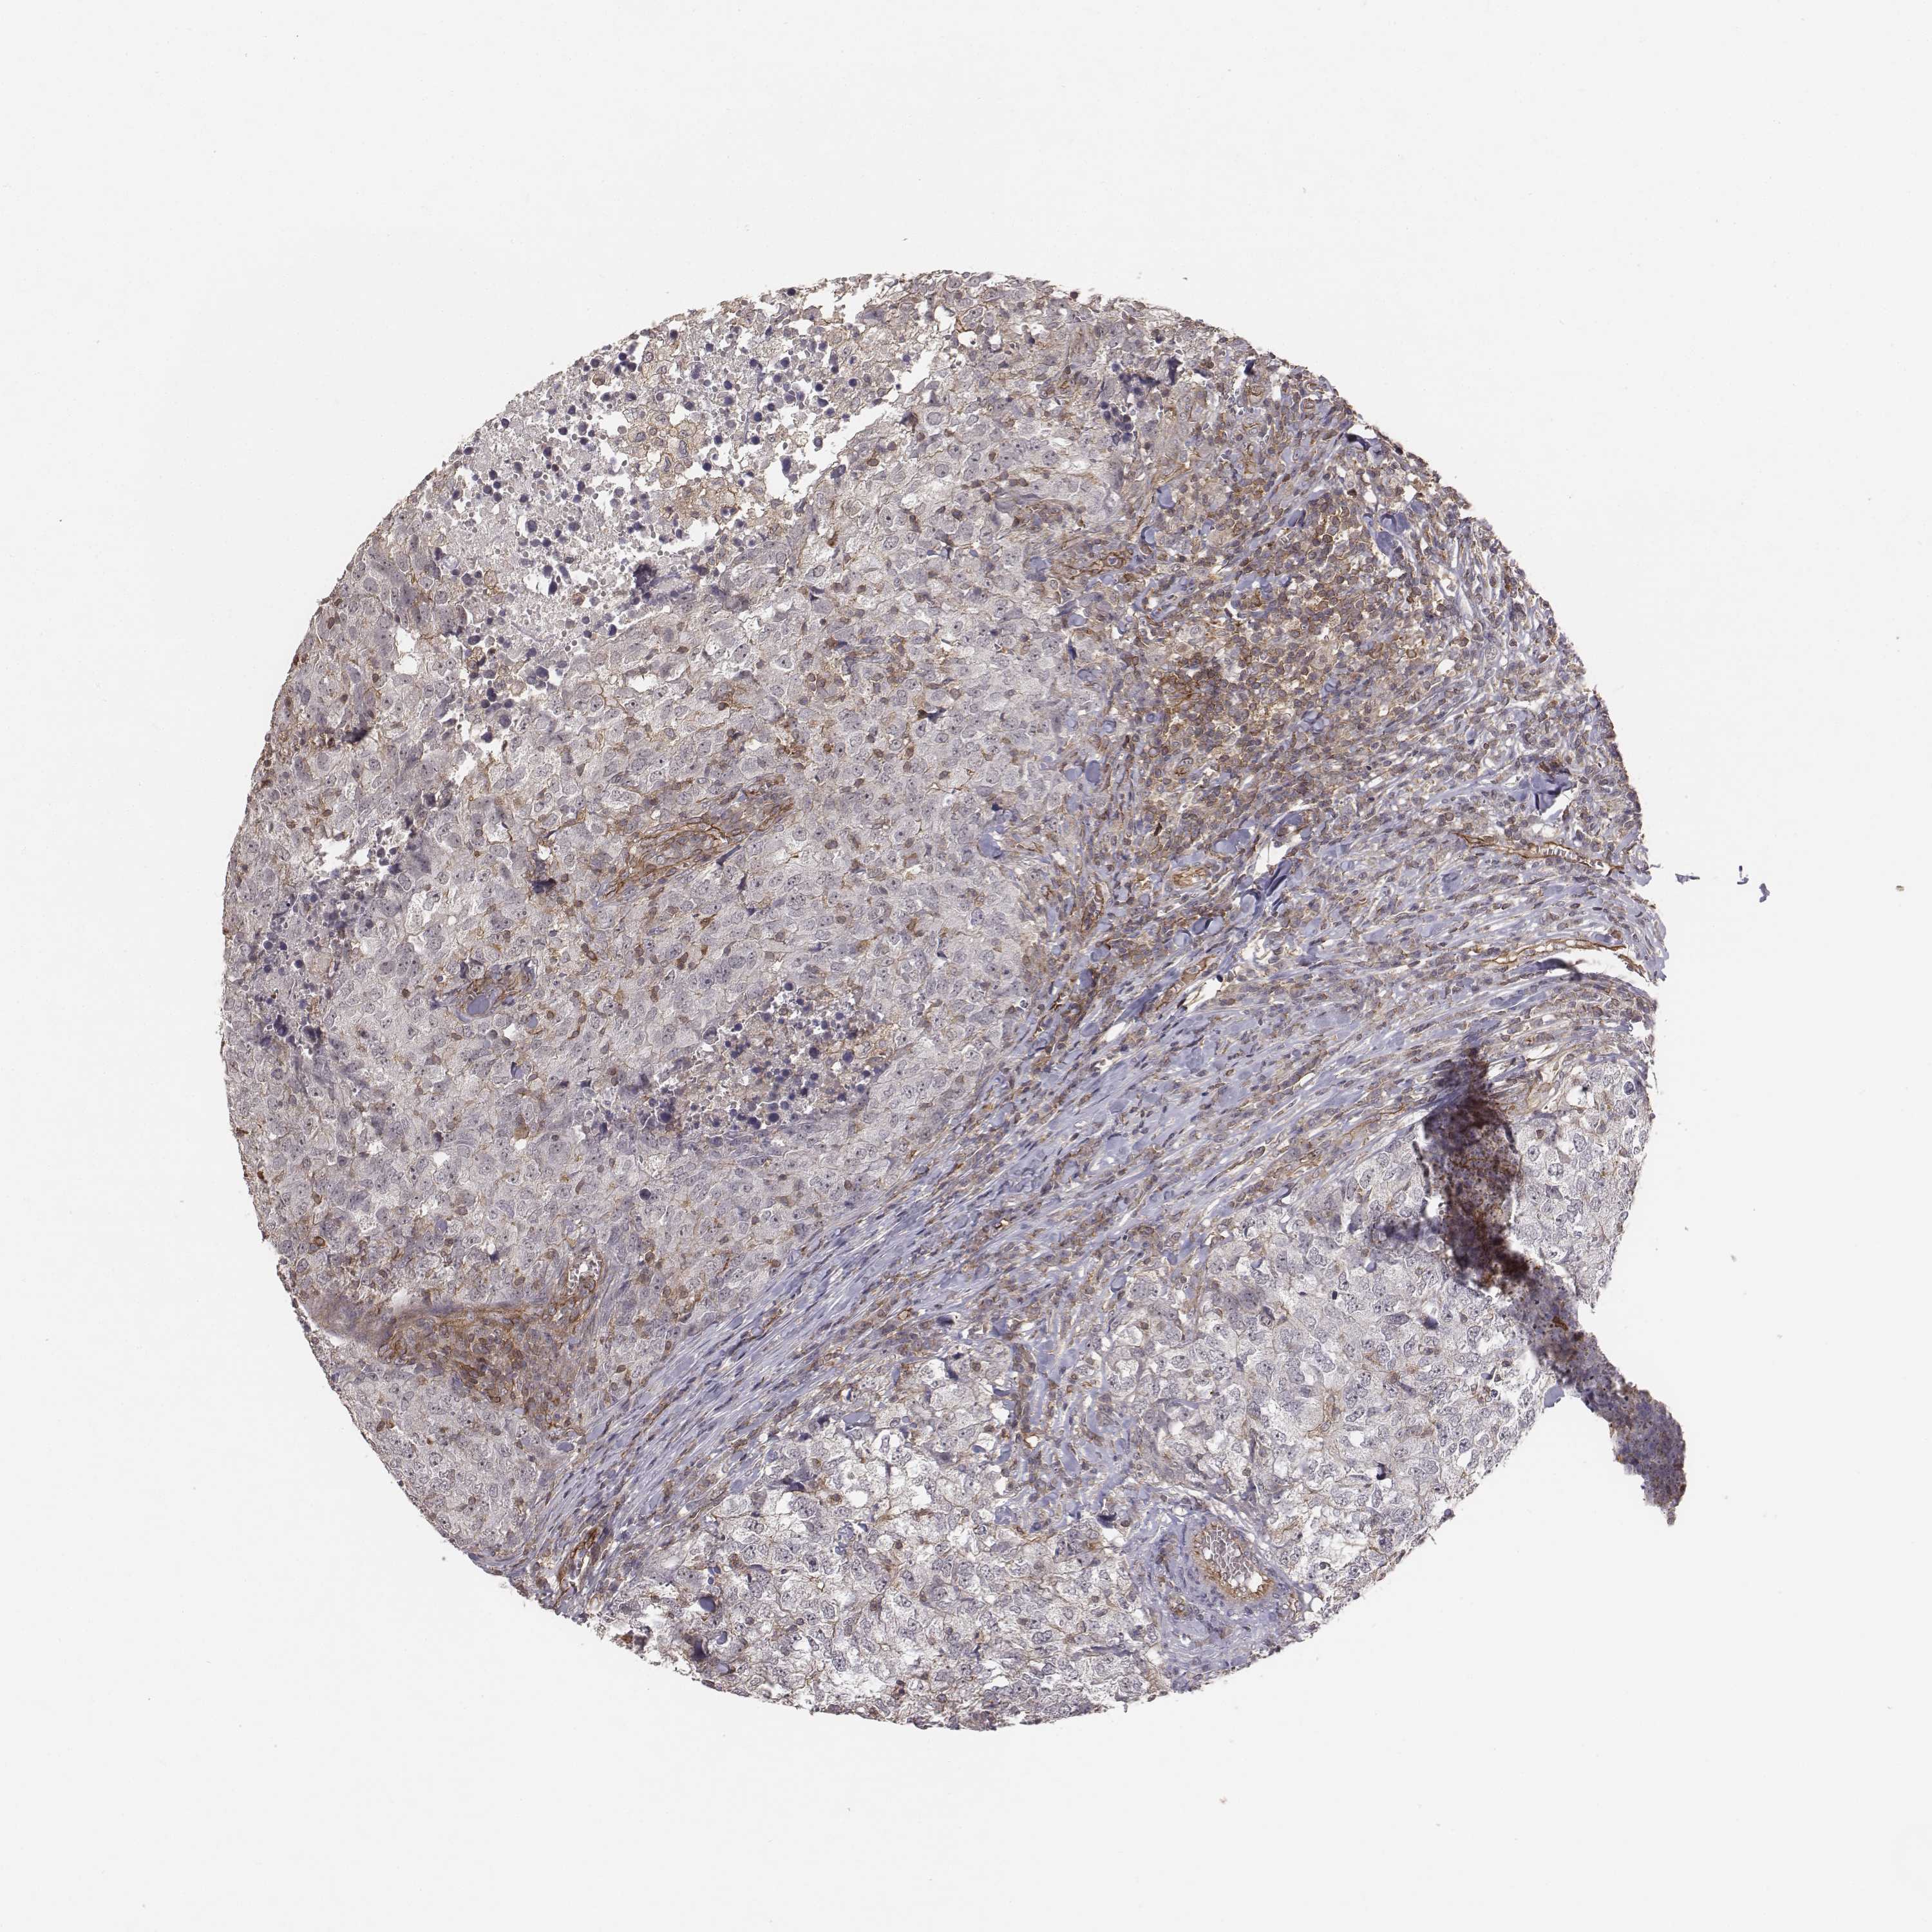

BRCA TCGA BRCA VALIDATION PROTEIN EXPRESSION